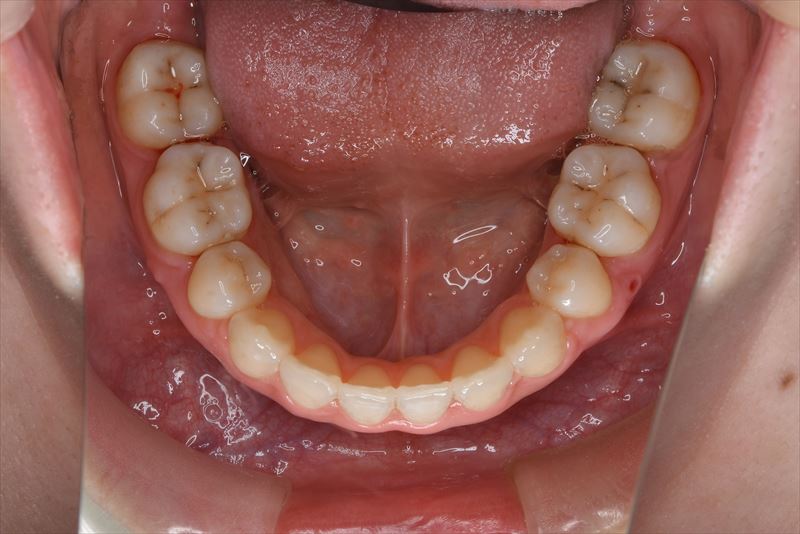

治療後

上顎両側4番抜歯、下顎両側4番抜歯、下顎両側8番抜歯

2年6か月、32回

臼歯のみの咬合、口唇の閉鎖が難しい状況でした。抜歯を行い前歯を牽引することで、良好な側貌と緊密な咬合を獲得できました。